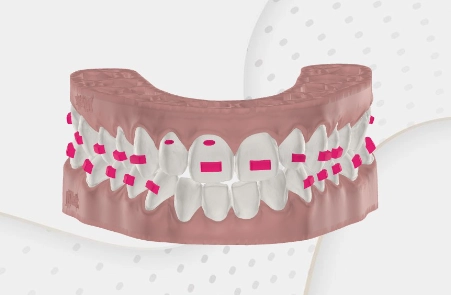

Hinter jeder erfolgreichen Aligner-Behandlung steht ein digitaler Plan. Mit modernster 3D-Technologie und gelenkzentrierter Diagnostik planen wir Ihre Zahnbewegungen präzise nach unserem Konzept KFO360° — noch bevor der erste Aligner gefertigt wird.

Wir kombinieren hochauflösende 3D-Scans mit Kiefergelenksdiagnostik, um eine Behandlung zu entwerfen, die zu Ihrem gesamten Kauapparat und Körper passt.

Expertengeführte Bewegungssimulation

Jede Zahnbewegung planen wir selbst — nicht die Aligner-Firma. Weil wir den Patienten kennen, passt jeder Schritt genau.

Individuelle Aligner-Herstellung

Ihre Aligner werden exakt nach dem Plan gefertigt — für optimalen Komfort und bestmögliche Ergebnisse.

Von digitalen Scans bis zu handgefertigten Alignern – wir vereinen Präzision, Sorgfalt und Erfahrung in jeder Phase Ihrer kieferorthopädischen Behandlung.

Wir nutzen diese Planung für jeden Aligner-Fall — besonders bei Erwachsenen, CMD-Problemen oder wenn frühere Behandlungen nicht erfolgreich waren.